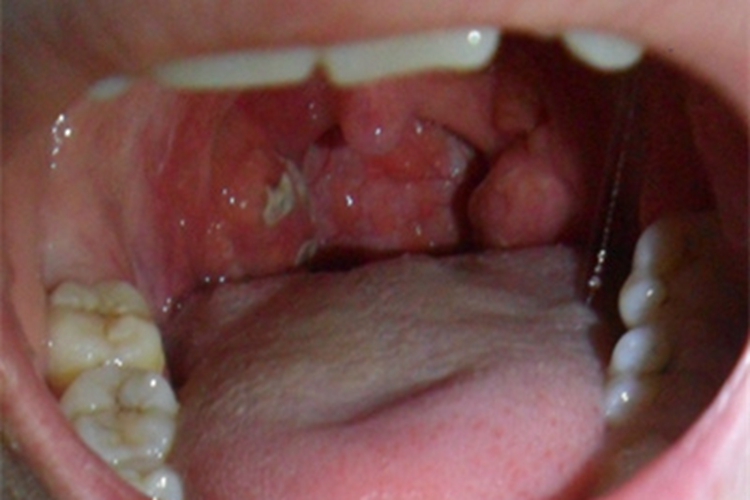

传染性单核细胞增多症可出现咽峡炎,可表现咽喉溃疡,呈黄白色,伴有疼痛感。

传染性单核细胞增多症发病期症状呈多样性,如全身不适、头痛、畏寒、鼻塞等。典型临床三联症为发热、咽峡炎和淋巴结肿大,可合并肝脾肿大。半数以上患者有咽峡炎症状,表现为咽喉红肿,伴有疼痛感,还可出现溃疡,表现为形状不规则的黄白色斑膜,周围黏膜充血发红。